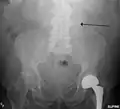

The faint outline of the calcified wall of an AAA as seen on a plain X-ray -